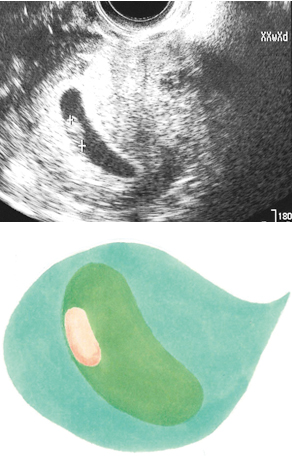

妊娠6週ころの超音波写真

心拍が確認できることもあります

小さな豆粒の赤ちゃん(胎芽)が細長く成長してきます。心拍を確認できることもありますが、まだ微弱です。超音波写真では豆粒ですが、実際は目や口、手、足のもとがつくられています。

妊娠6週過ぎには、胎嚢の中に赤ちゃんの姿が見えるようになります。これが「胎芽」。見えないときは妊娠週数の誤差が主な原因ですが、胎嚢は完成していても胎芽ができないこともあります。

妊娠6週ごろから、赤ちゃんの心拍が認められるようになります。6週以降安定した心拍が続いていれば、流産の確率は低くなります。